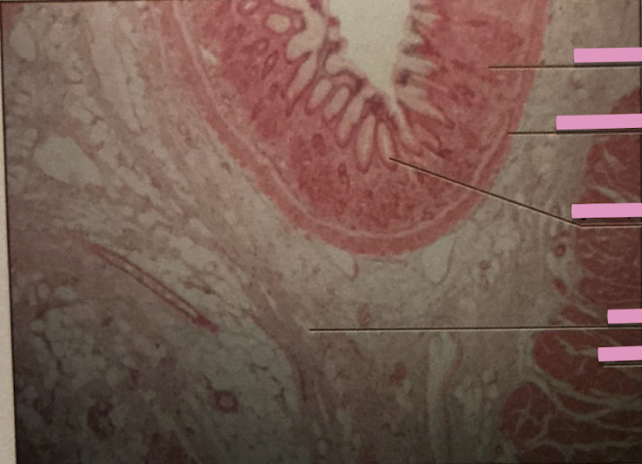

taste buds at 40x

taste buds at 400x

taste buds

clusters of encapsulated gustatory receptor cells onf surface of tongue

papillae

concentrated on surface of peg-like projections called ______

gustatory epithelial cells

receptor cells for taste

basal epithelial cells

stem cells dividing to produce new gustatory epithelial cells